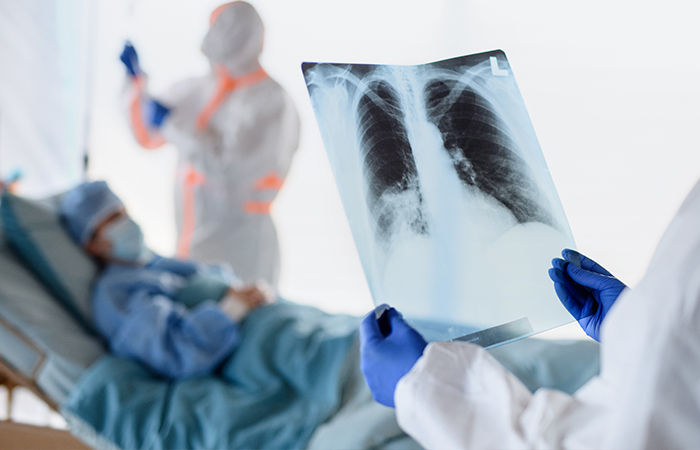

ટીબી મુખ્યત્ત્વે ફેફસાને અસર કરે છે. તે શરીરના અન્ય વિવિધ ભાગોને પણ અસર કરી શકે છે, જેને પછી એક્સટ્રાપલ્મોનરી ટીબી તરીકે ઓળખવામાં આવે છે. આ જ્યારે હાડકાને અસર કરે છે, ત્યારે તે ટ્યુબરક્યુલોસ ઓસ્ટીયોમેલિટીસ અથવા સાદી ભાષામાં હાડકાનો ટ્યુબરક્યુલોસિસ (ટીબી) તરીકે ઓળખાય છે. હાડકાનો ટીબી શરીરના વજનને આધાર આપતા હાડકા, સાંધાઓ, કરોડરજ્જુના મણકાને સૌથી વધુ અસર કરે છે.

આ અંગે સિવિલિ મેડિસિટીમાં આવેલી સ્પાઈન ઈન્સ્ટિટ્યુટના ડિરેક્ટર ડૉ. પીયૂષ મિત્તલે જણાવ્યું કે, 'હાલ સિવિલની સ્પાઈન ઈન્સ્ટિટયુટમાં આવતા સરેરાશ 30માંથી 1 દર્દી સ્પાઈનમાં ટીબીની સમસ્યા સાથે આવે છે. સ્પાઈનમાં ટીબીનું નિદાન થાય અને તકેદારી રાખવામાં આવે નહીં તો લકવો, હાથ-પગ કામ કરતાં બંધ થઇ જવા, અતિશય નબળાઈ આવવા સહિતનું જોખમ રહે છે. અલબત્ત, આ પ્રકારની સમસ્યા કામચલાઉ હોય છે. સમયસર સારવાર શરૂ થાય તો તેમાંથી ઝડપથી સાજા પણ થઈ શકાય છે. ટીબીથી સાજા થવું શક્ય છે.'